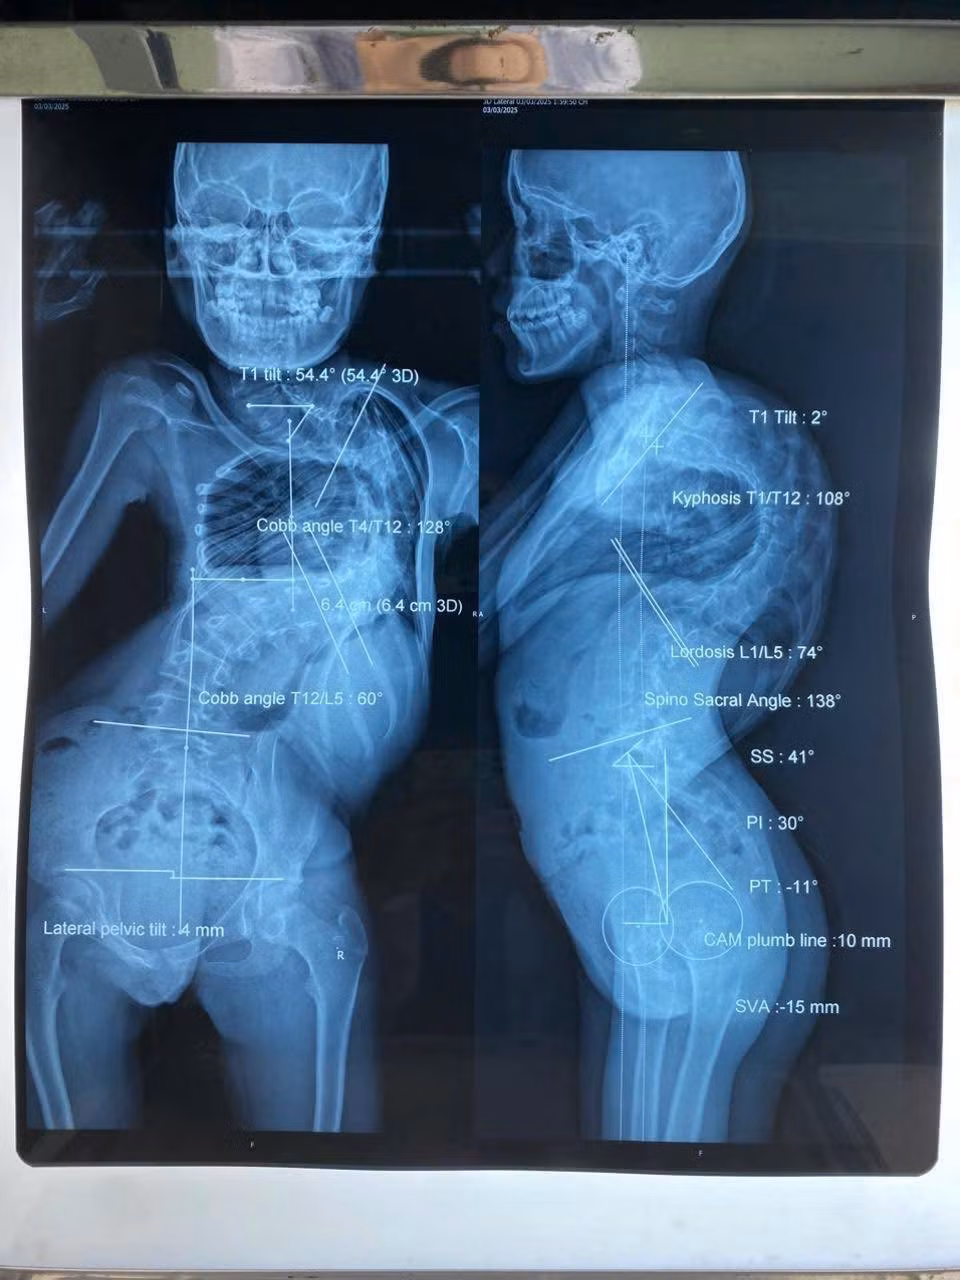

Khác với bé L., thách thức của bé Y.T (13 tuổi) đến từ thể trạng quá yếu. Bé chỉ nặng 28 kg do suy dinh dưỡng nặng, mắc hội chứng hạn chế hô hấp, cột sống cong đến 128 độ và gù 108 độ khiến lồng ngực bị chèn ép liên tục, chỉ có thể nằm sấp khi ngủ.

Hình ảnh cột sống cong vẹo trên phim chụp của các bệnh nhi - Ảnh BVCC